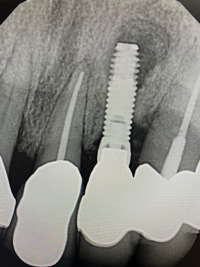

In this case, a dental implant that had been placed 10 years prior was functional, stable, and esthetically acceptable to the patient. However, a significant fistula was present on the facial-apical aspect of the ridge in the maxillary lateral incisor area. This area was painfully sensitive to touch and demonstrated purulence when squeezed. To evaluate the lesion, first, a conventional digital radiograph was acquired, which revealed an apical radiolucency at the apex of the implant (Figure 1). Further analysis using cone-beam computed tomography (CBCT) demonstrated a fistula from that site to the oral environment (Figure 2). Treatment options were discussed, including removal of the implant, followed by grafting, a healing period, and replacement of the implant and implant-retained crown. If this option was selected, a transitional appliance would need to be created. Another option was to attempt to salvage the implant and implant crown by treating the infection and grafting the site to create a new boney wall and eliminate the fistula. Ultimately, the patient accepted this option to attempt to salvage the fixture and crown.

In this case, the procedure was precise, and the patient experienced minimal postoperative discomfort. An immediate postoperative digital radiograph was acquired to evaluate the radiolucent appearance of the grafted apical defect (Figure 12). After 8 weeks, the tissue appeared to be healing quickly and predictably (Figure 13), and a follow-up sagittal CBCT analysis demonstrated a new wall forming where the dehiscence had been present (Figure 14). The patient was recalled again after 5 months for radiographic analysis and intraoral evaluation, which revealed that the healing was progressing without complication (Figure 15 through Figure 18).

(1.) Preoperative radiographic evaluation demonstrating a large radiolucency at the apical third of the body of an implant fixture replacing the patient’s maxillary left lateral incisor. The implant was stable, and the prosthesis was deemed esthetically acceptable by the patient.

Figure 1

(12.) Immediate postoperative digital radiograph demonstrating the graft material in place.

Figure 12